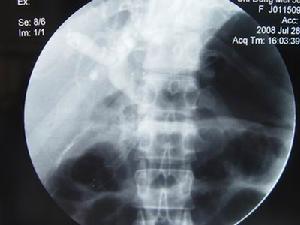

其它輔助檢查: 1.胃腸鋇餐及十二指腸低張造影檢查 有時可見十二指腸外上方有膽囊壓跡及其第一二段交界處有增粗的膽總管壓跡,十二指腸乳頭增大,黏膜呈不規則紊亂或充盈缺損。胰頭癌者可見十二指腸圈擴大十二指腸內側壁“僵硬”受壓變形或部分性梗阻呈“∑”形,但典型表現者少見。